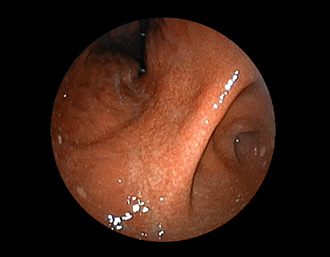

胃角部小弯の潰瘍。潰瘍辺縁は平滑で、白苔は部分的に薄い箇所もあり、全周性に再生上皮を認める。

(通常画像)